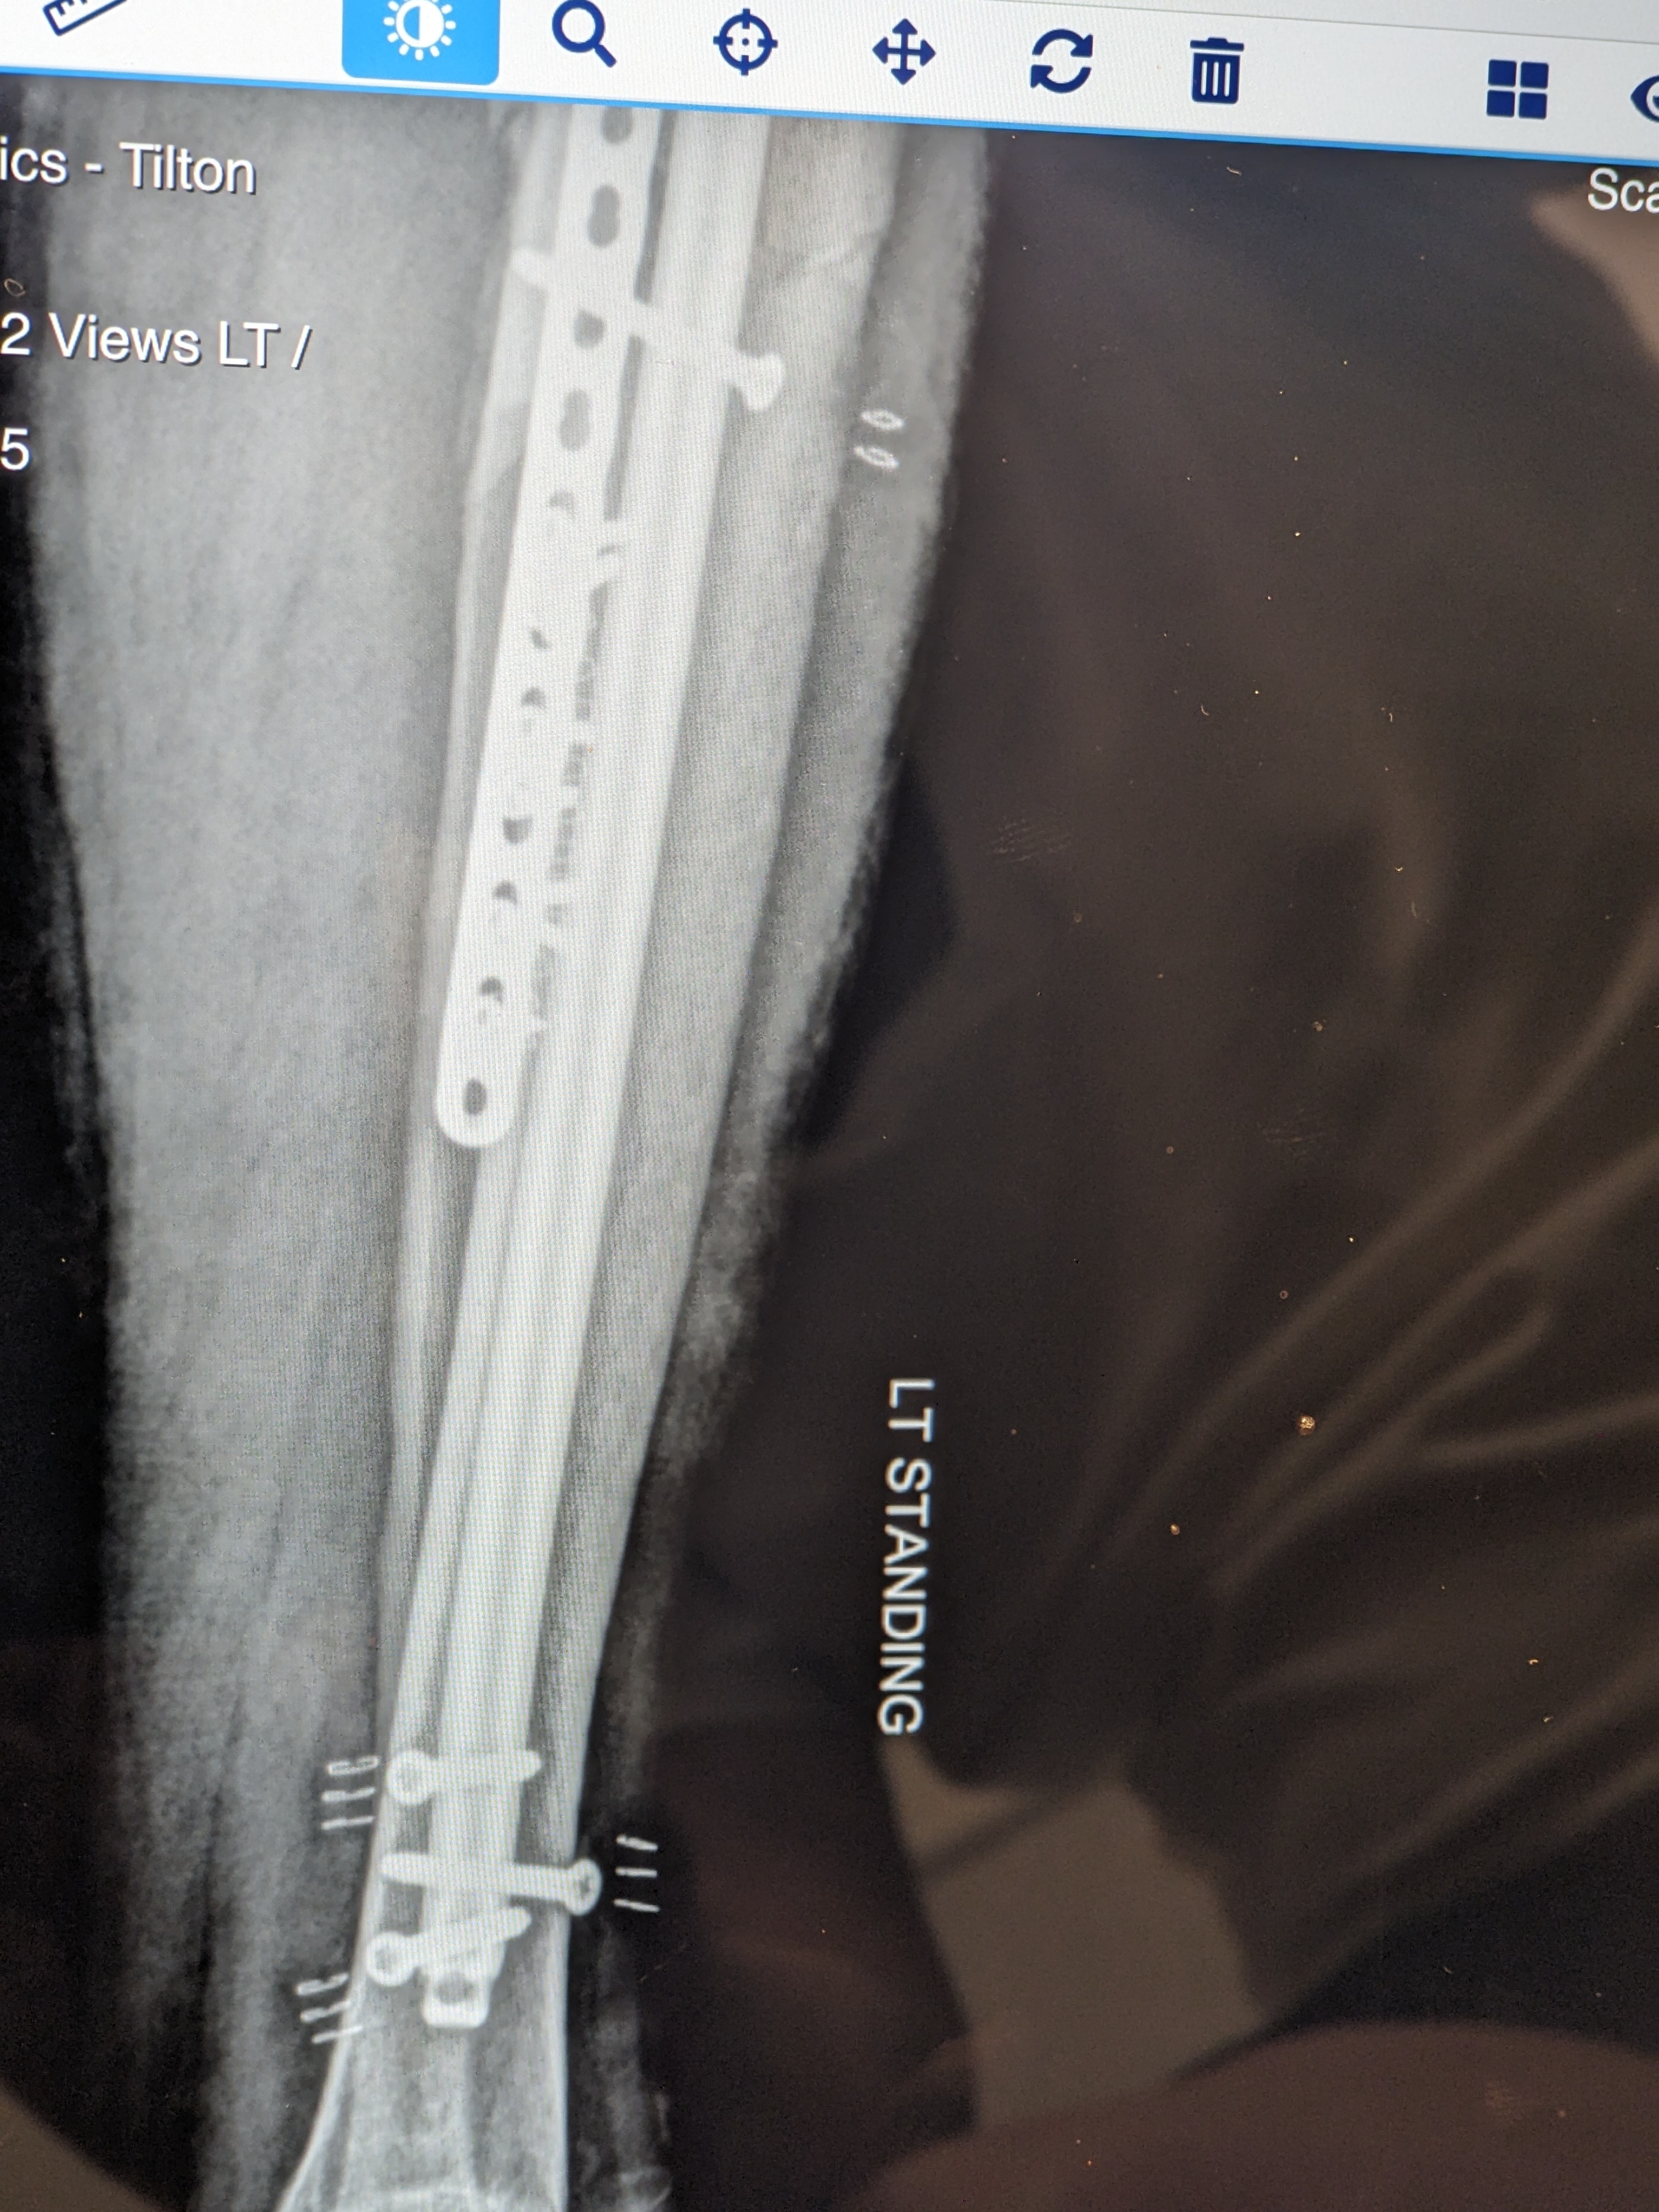

I got my original hardware back that was removed and replaced with the Superduty stuff. I wonder if these items can be resold to third world regions in need of medical implants?

New hardware is providing more stability. Now only hope the crunched Tibia begins to mend.